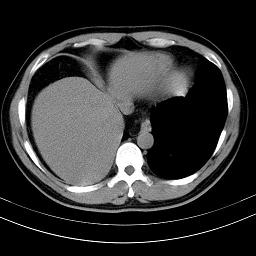

标题: CT18388:肝脏膈肌间隙内大量脂肪密度影 [打印本页]

标题: CT18388:肝脏膈肌间隙内大量脂肪密度影

是脂肪不是气体,有时候会碰到这样的病人,脂肪过多吧。

腹腔脂肪沉积过多

膈下脂肪沉积。

考虑膈下脂肪沉积。

激素治疗的病人容易脂肪沉积